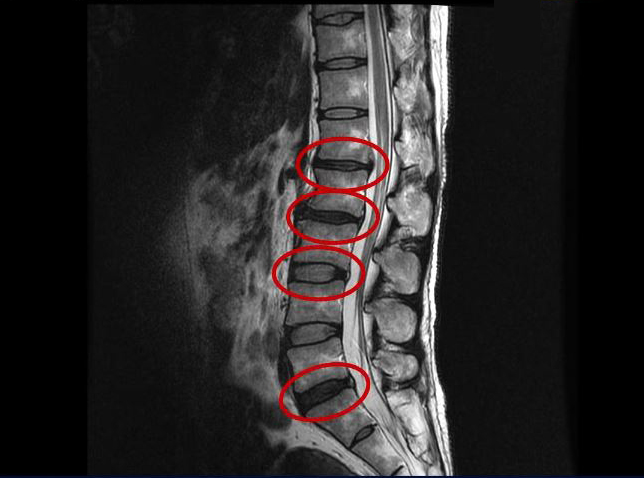

그런데 이 환자분의 MRI를 보면 여러 마디에 퇴행성디스크가 있습니다.

<1-2번>

<2-3번>

<3-4번>

<5번-꼬리뼈 1번>

이 환자분은 MRI상으로 거의 대부분 마디의 디스크가 퇴행되고 수핵이 밀려나와 있으며, 정상적인 허리 마디는 4-5번 하나 정도입니다. 그렇기 때문에 MRI만 보면 아마 대부분의 병원에서 허리디스크탈출 또는 퇴행성디스크로 인한 허리통증 및 다리통증으로 진단하고 치료할 것입니다. 이분도 그래서 20년간 그런 치료를 무수히 많이 받았으나 그 어떤 치료도 별 도움이 되지 않았습니다.